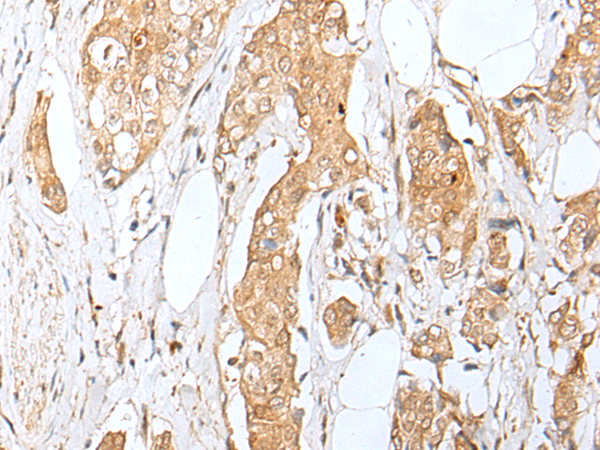

IHC (Immunohistochemisry)

(The image is immunohistochemistry of paraffin-embedded Human breast cancer tissue using (ZNF34 Antibody) at dilution 1/40.)